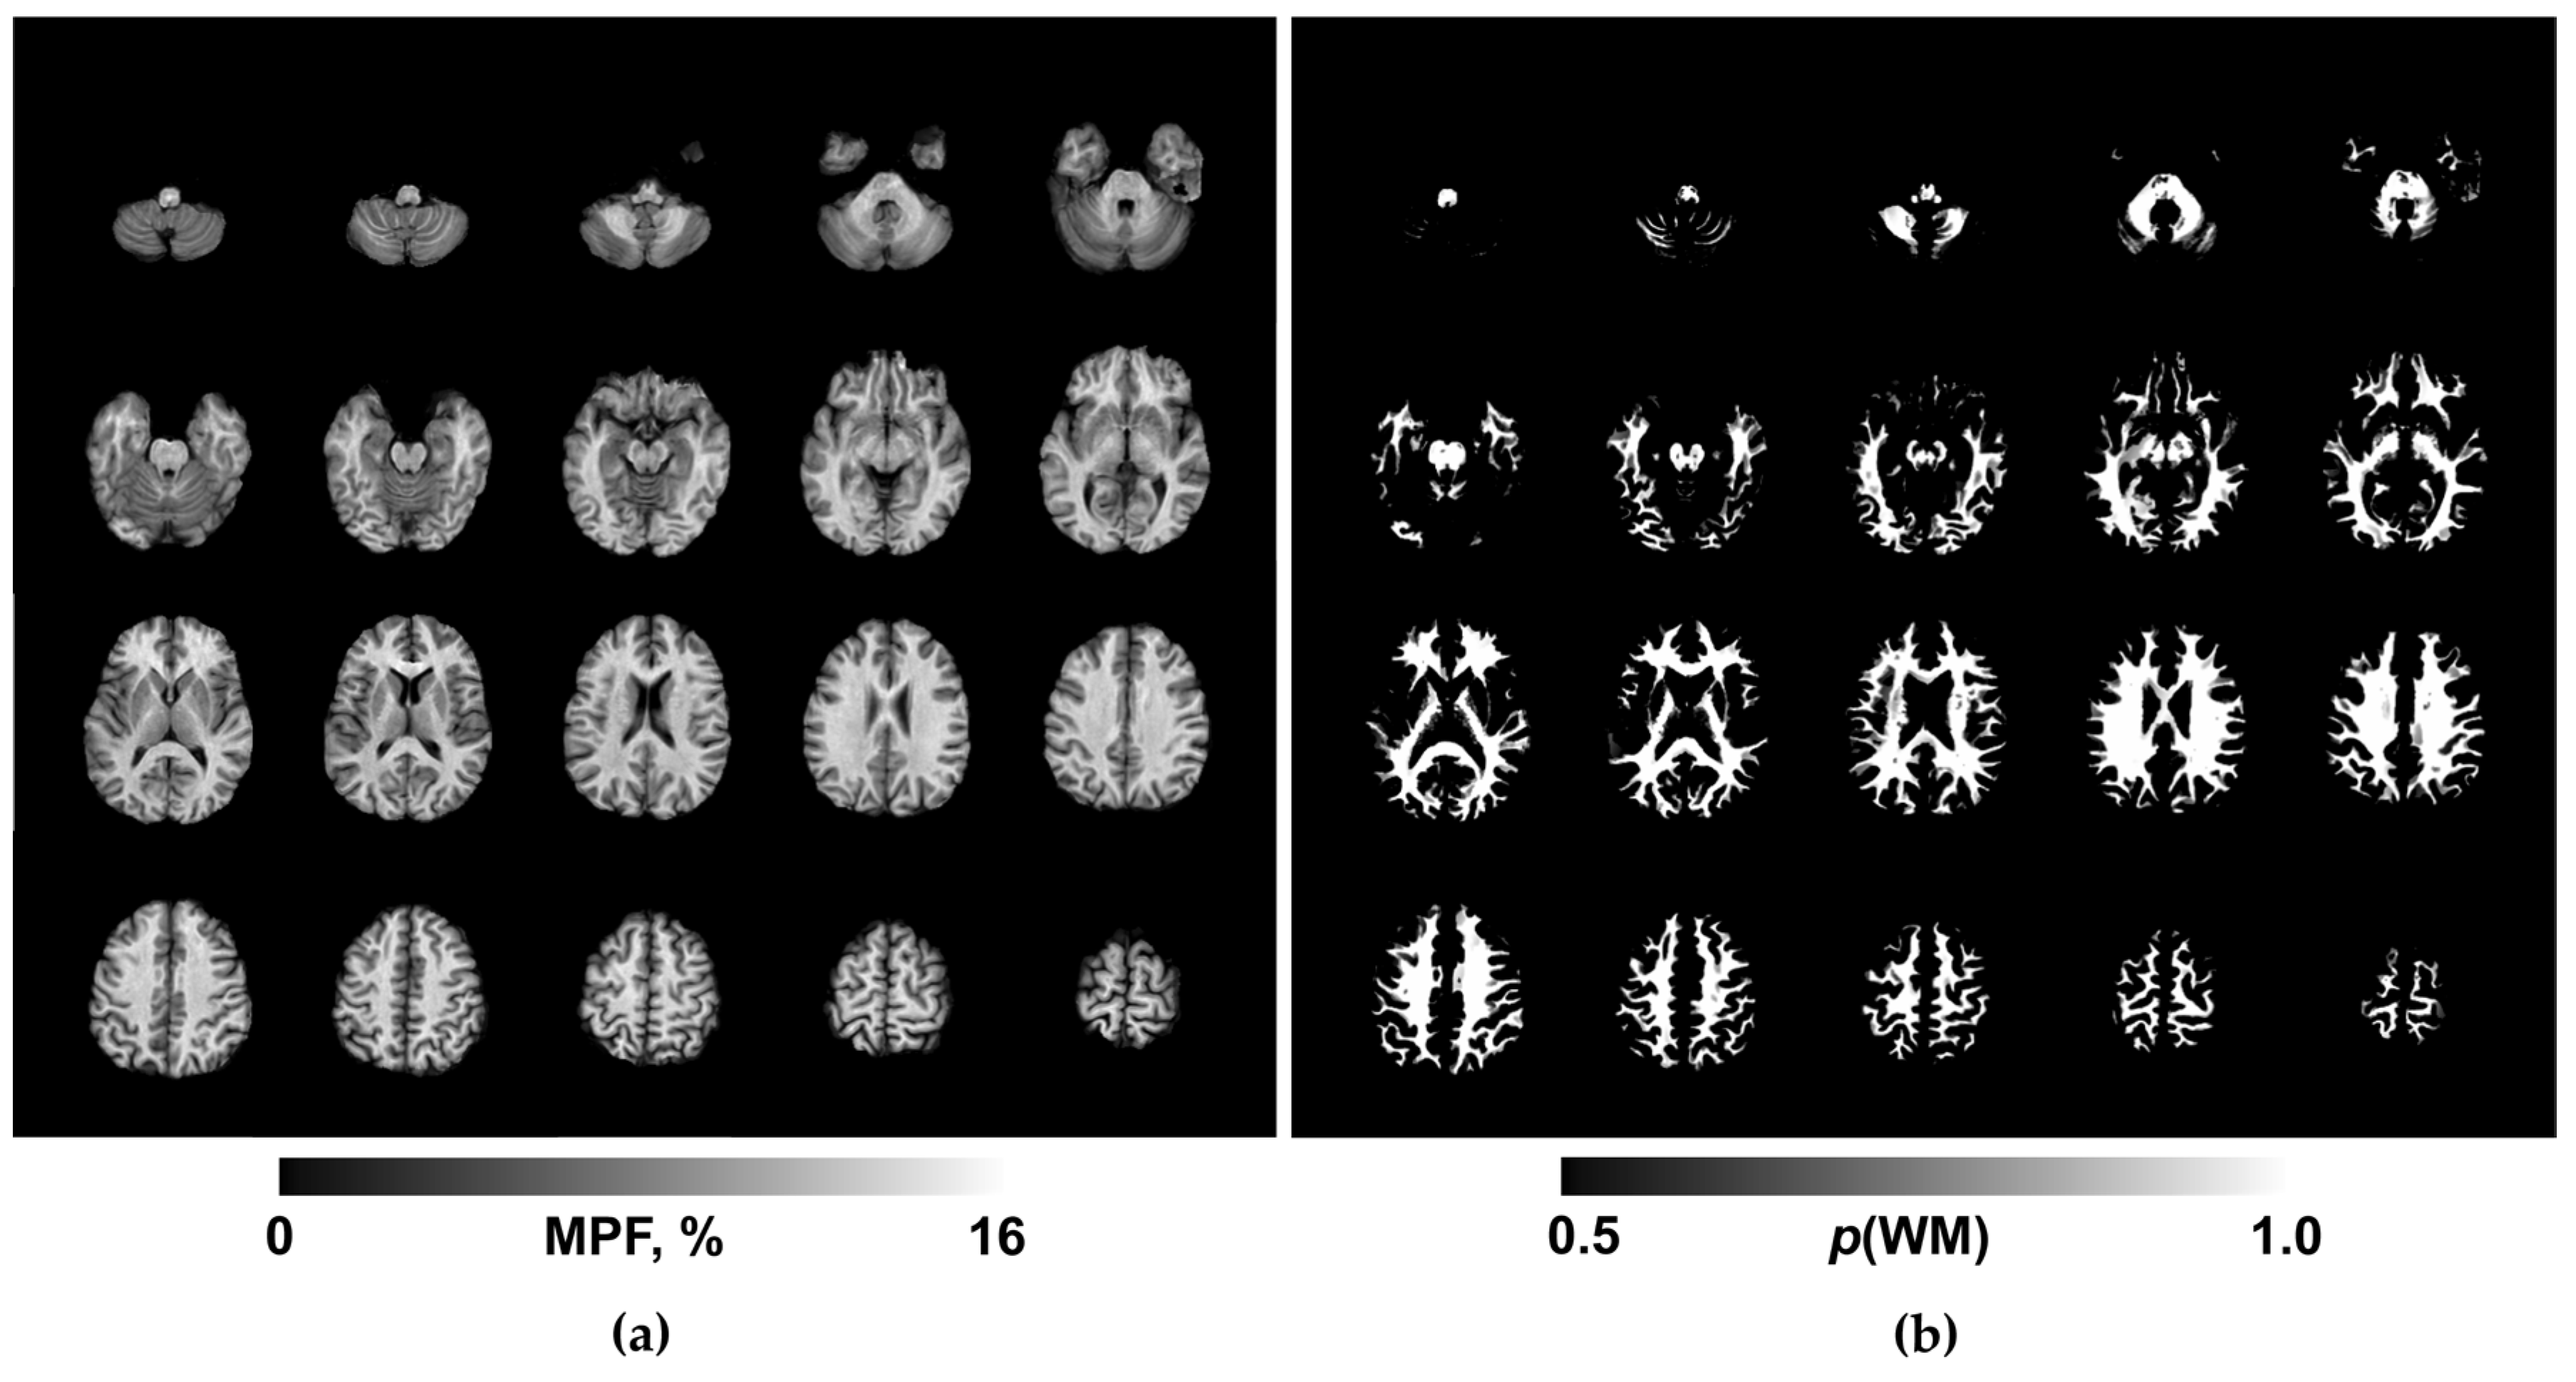

Routine clinical images were reviewed by a board-certified radiologist for the presence of focal, diffuse, or structural abnormalities. MPF maps were reconstructed using custom C++ language software (available at https://www.macromolecularmri.org/) based on the single-point synthetic reference algorithm [23,33]. The two-pool model parameter constraints were set according to the earlier implementations for 1.5 T [29,34]: cross-relaxation rate constant R =19 s−1; T2 of bound macromolecular protons, T2B = 10 μs; and the product of the relaxation rate R1 and T2 of free water protons, R1T2F = 0.055. No correction of B0 and B1 field inhomogeneities was performed, because the effect of these corrections at 1.5T is negligibly small [35]. An example MPF map obtained using the above acquisition and processing protocol is presented in Fig. 1a. The resulting 3D MPF maps were post-processed using FSL software (FMRIB Software Library v. 6.0; Oxford Centre for Functional Magnetic Resonance Imaging of the Brain, University of Oxford, Oxford, England; available at www.fmrib.ox.ac.uk/fsl/). The post-processing steps included skull stripping using the brain-extraction tool (BET) [36] and tissue segmentation using the fast automated segmentation tool (FAST) [37] under the single-channel three-class approach with the Markov random field parameter 0.1 and four iterations for bias field removal. The resulting WM probability maps (exemplified in Fig. 1b) were binarized at the probability threshold of 0.9 to obtain conservative WM masks for MPF quantitation.

An example of the maps used in the work is shown in Figure 1.

Figure 1. Example 3D MPF (a) and WM probability (b) maps obtained from a BD patient. Axial cross-sections of a 3D volume are presented with the step of 6 mm (every second cross-section).